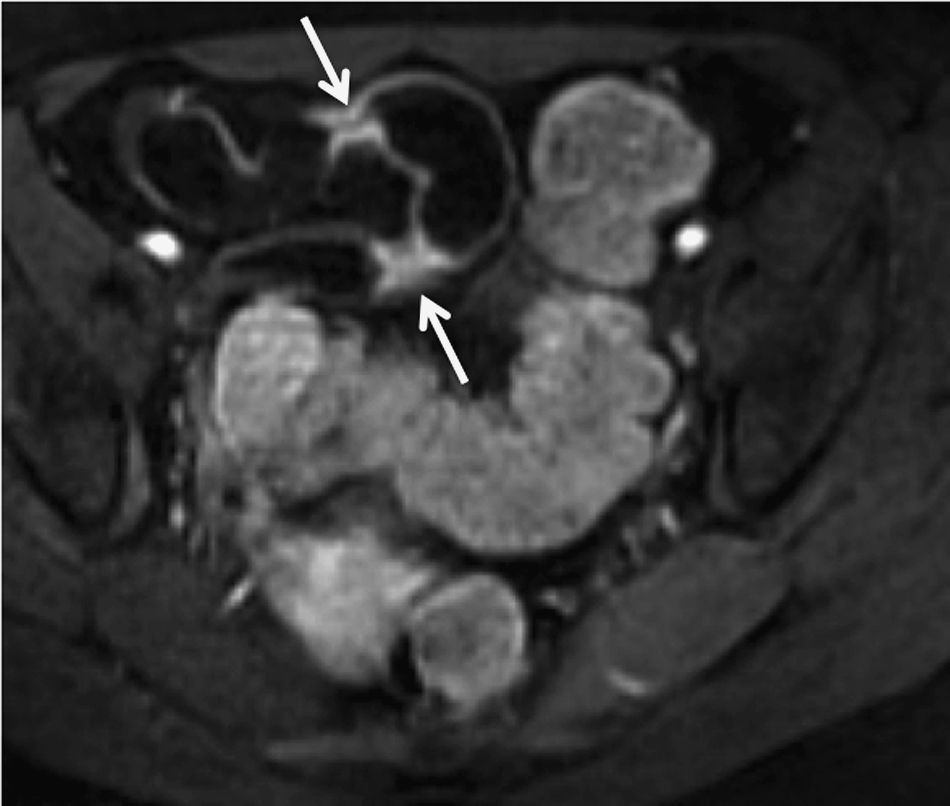

Radiology with oral contrast, or enteroclysis, have traditionally been the techniques of choice in the examination of the small intestine, due to the excellent visualisation of the mucosal pattern. However, the absence of extra-luminal information and the use of ionising radiation have replaced these examinations with sectional techniques which enable the abdominal cavity to be viewed with good resolution. Magnetic resonance enterography is a simple technique, with no ionising radiation, provided quality images, distends the intestinal lumen well by the administration of non-reabsorbable oral substances, minimises peristalsis, and establishes a protocol which includes sequences with intravenous contrast. These properties can be used in patients with Crohn's disease, achieving good diagnostic precision in the assessment of activity and monitoring of treatment, in intestinal obstruction, in the suspicion of small intestine tumours, and in paediatric patients due to it being harmless.